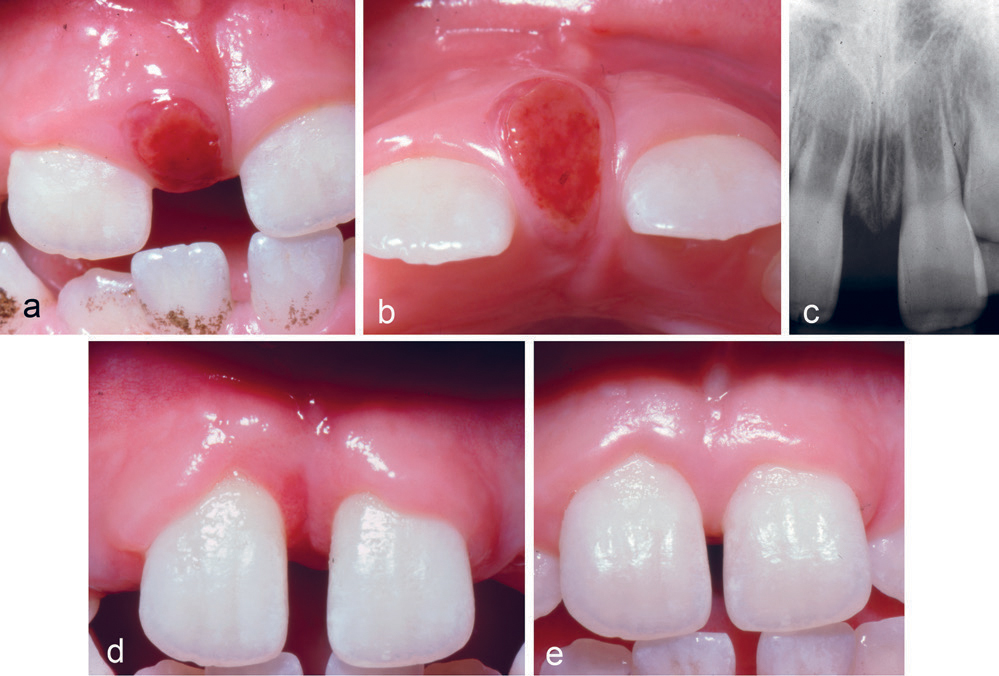

Kasus 2

En åtte år gammel gutt var henvist fra egen tannlege for fjerning av lesjon mellom tennene 11 og 21. Lesjonen hadde vokst langsomt i løpet av seks måneder etter at tenne 51 og 61 var ekstrahert. Klinisk undersøkelse viste et 4–5 mm diastema samt en rød-brun lesjon mellom 11 og 21 (figur 2a, b). Det var ikke ben-nedbrytning mellom tennene (figur 2c). Lesjonen ble fjernet, og blottlagt benoverflate ble dekket med en salveveke. Den histologiske undersøkelsen bekreftet diagnosen PKCG. Ved kontroll etter en måned var der betydelig redusert diastema (figur 2d), og avsluttende kontroll viste normale forhold uten residiv tolv måneder postoperativt (figur 2e).

Figur 2. Kasus 2. en åtte år gammel gutt med PKCG mellom tann 11 og 21 uten marginal bennedbrytning (a, b, c). Foto en måned postoperativt (d). Foto 12 måneder postoperativt (e).